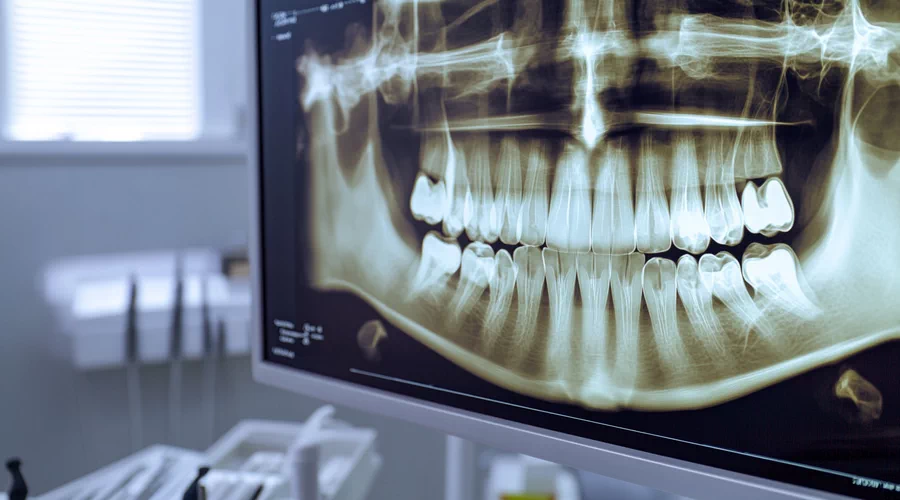

Maxillofacial surgery focuses on diagnosing and treating conditions affecting the facial skeleton, jaws, mouth, and surrounding structures. When combined with plastic surgery, it also addresses cosmetic concerns, restoring balance, symmetry, and confidence. Vladimir Soyfer European Maxillo Facial and Plastic Surgeon blends medical precision with aesthetic expertise to deliver both functional and visual improvements.

One of the most common areas of treatment includes jaw alignment and bite problems. Patients with misaligned jaws may experience difficulty chewing, speaking, or breathing, along with facial asymmetry. Conditions such as overbite, underbite, crossbite, and open bite are often treated through corrective jaw surgery.

By repositioning the jaw, patients can achieve improved oral function, reduced pain, and a more balanced facial appearance. These procedures are often life-changing, especially for individuals who have struggled with functional limitations for years.

Patients who have lost teeth due to injury, decay, or disease often require dental implants for long-term restoration. However, insufficient jawbone can make implant placement challenging. Maxillofacial surgeons are uniquely qualified to perform bone grafting procedures that rebuild the jawbone, creating a stable foundation for implants.